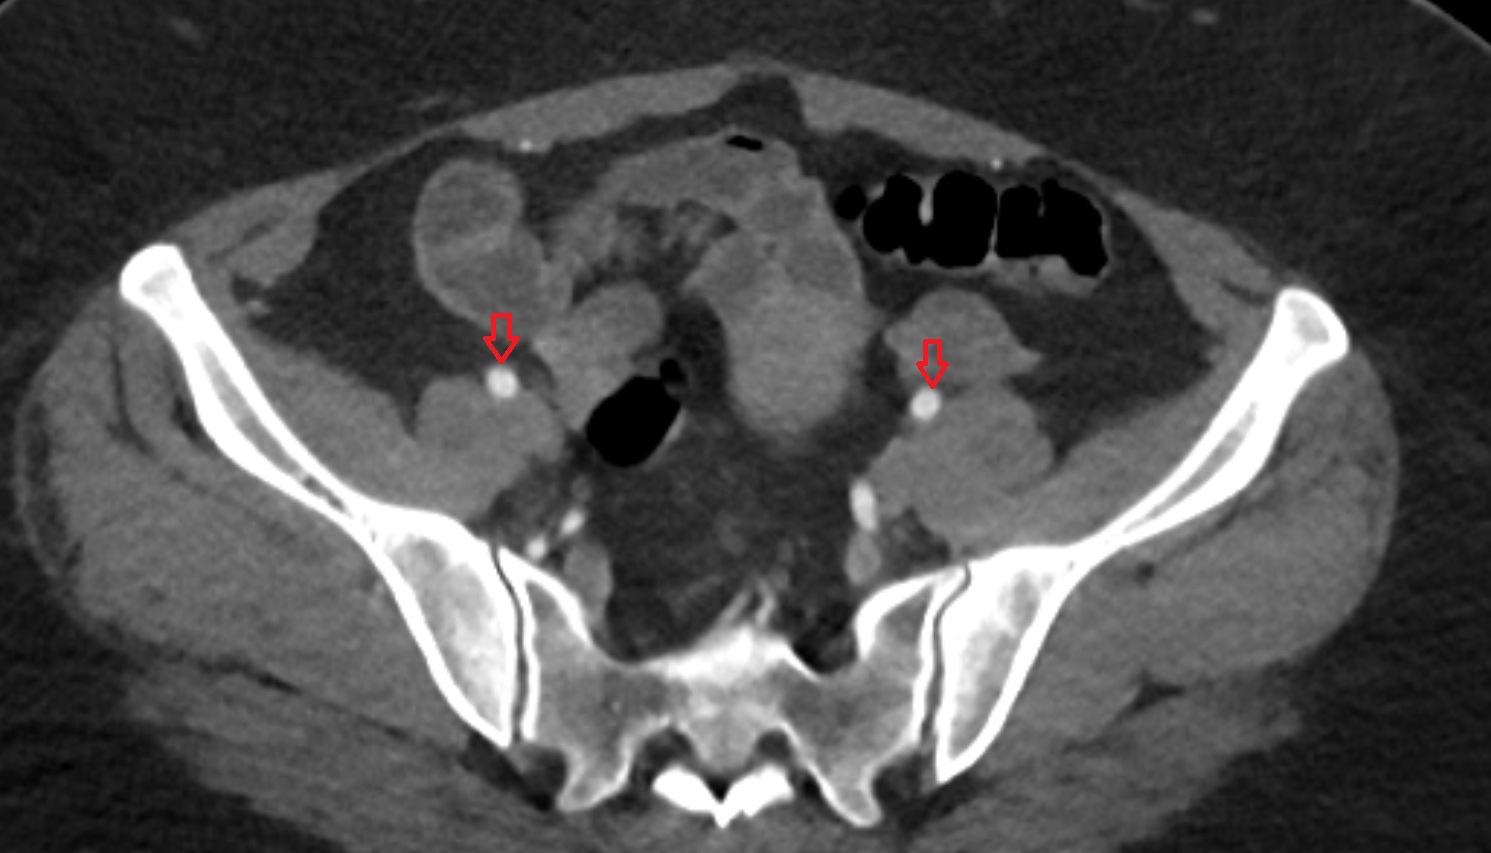

- External iliac artery

- Internal iliac artery

- External iliac vein

- Internal iliac vein

- Common iliac vein

- common iliac artery